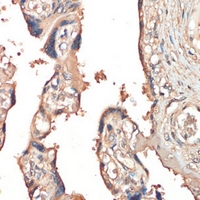

Immunohistochemical analysis of HGFL staining in human placenta formalin fixed paraffin embedded tissue section. The section was pre-treated using heat mediated antigen retrieval with sodium citrate buffer (pH 6.0). The section was then incubated with the antibody at room temperature and detected using an HRP conjugated compact polymer system. DAB was used as the chromogen. The section was then counterstained with haematoxylin and mounted with DPX. -